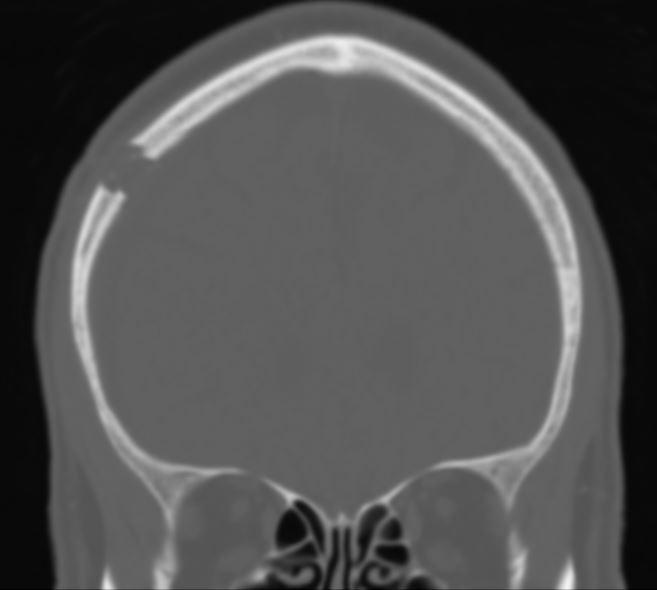

Bohrlochtrepanation CT

Abbildung einer coronaren CT Bildgebung im Knochenfenster bei einem Patienten nach durchgeführter rechtsseitiger Bohrlochtrepanation.